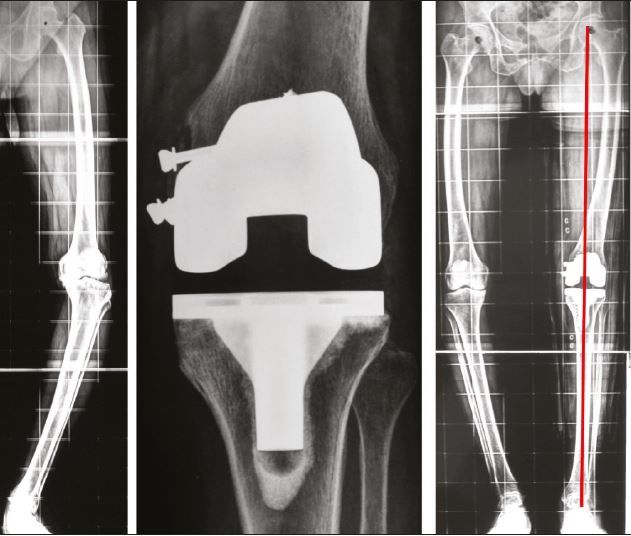

3. Extra-articular femoral and/or tibial deformity needs to be identified and appropriate extra-articular or intra-articular correction performed8

If extra-articular deformity (EAD) is >20 degrees, close to the joint, and resection likely to damage LCL attachment or if the distal tibial axis falls outside of tibial plateau, then EA osteotomy may be required.(Figs 4-6)

- If these are released and deformity persists, it implies that there is a tibial EAD. This should have been detected and anticipated in the planning stage. Obtain a rectangular extension gap by re-cutting proximal tibia. Any residual varus deformity is corrected by closed-wedge osteotomy at apex of deformity usually in the tibial metaphysis.